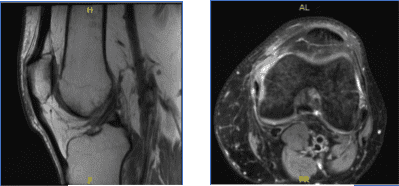

MRI-3T Rodilla Izquierda sin contraste

Se presentaron resultados para la resonancia magnética y mostraron esguince del ligamento colateral medial, sin evidencia de desgarros de alto grado. Desgarro vertical longitudinal que afecta al tercio externo del cuerpo y al menisco medial del cuerno posterior.